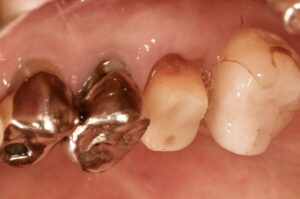

根管治療後の写真です。

治療により歯の中はきれいになったのですが、

歯ぐきに炎症が残っています。

これでは骨の中の病巣も治っていません。

病巣が大きいため、歯の外側が汚染している可能性があります。

つまり、根管の中を治療しても治らないのです。